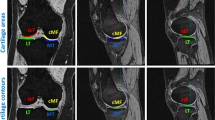

Diffusion tensor imaging of physis and metaphysis can be used as a biomarker to predict height change in the pediatric population. Current application of this technique requires manual segmentation of the physis which is time-consuming and introduces interobserver variability. UNET Transformers (UNETR) can be used for automatic segmentation to optimize workflow. Three hundred and eighty-five DTI scans from 191 subjects with mean age of 12.6 years ± 2.01 years were retrospectively used for training and validation. The mean Dice correlation coefficient was 0.81 for the UNETR model and 0.68 for the UNET. Manual extraction and segmentation took 15 min per volume, whereas both deep learning segmentation techniques took < 1 s per volume and were deterministic, always producing the same result for a given input. Intraclass correlation coefficient (ICC) for ROI-derived femur diffusion metrics was excellent for tract count (0.95), volume (0.95), and FA (0.97), and good for tract length (0.87). The results support the hypothesis that a hybrid UNETR model can be trained to replace the manual segmentation of physeal DTI images, therefore automating the process.

Jaimes C, Berman JI, Delgado J, et al. Diffusion-tensor imaging of the growing ends of long bones: pilot demonstration of columnar structure in the physes and metaphyses of the knee. Radiology. 2014; 273(2):491-501. PMID: 25102295

Bedoya MA, Delgado J, Berman JI, et al. Diffusion-Tensor Imaging of the Physes: A Possible Biomarker for Skeletal Growth-Experience with 151 Children. Radiology. 2017; 284(1):210-218. PMID: 28156202

Barrera CA, Bedoya MA, Delgado J, Berman JI, Chauvin NA, Edgar JC, Jaramillo D. Correlation between diffusion tensor imaging parameters of the distal femoral physis and adjacent metaphysis, and subsequent adolescent growth. Pediatr Radiol. 2019 Aug;49(9):1192-1200. https://doi.org/10.1007/s00247-019-04443-z. Epub 2019 Jun 8. PMID: 31177318.

Duong P, Mostoufi-Moab S, Raya JG, Jaimes C, Delgado J, Jaramillo D. Imaging Biomarkers of the Physis: Cartilage Volume on MRI vs. Tract Volume and Length on Diffusion Tensor Imaging. J Magn Reson Imaging. 2020 Aug;52(2):544–551. https://doi.org/10.1002/jmri.27076. Epub 2020 Feb 10. PMID: 32039525; PMCID: PMC7410391.

Jaramillo D, Duong P, Nguyen JC, Mostoufi-Moab S, Nguyen MK, Moreau A, Barrera CA, Hong S, Raya JG. Diffusion Tensor Imaging of the Knee to Predict Childhood Growth. Radiology. 2022 Jun;303(3):655–663. https://doi.org/10.1148/radiol.210484. Epub 2022 Mar 22. PMID: 35315716; PMCID: PMC9131176